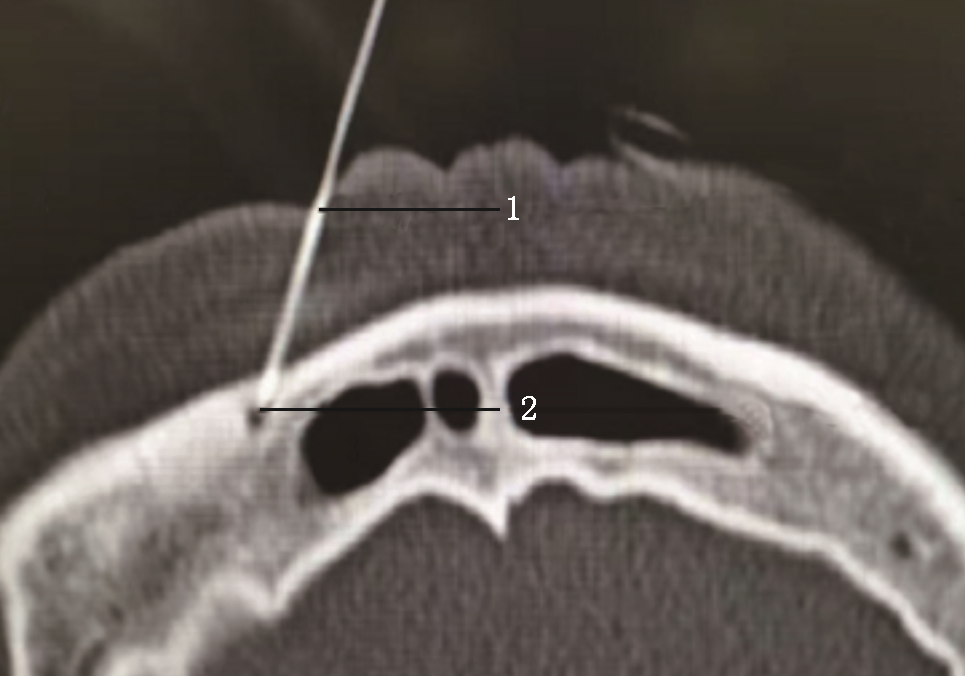

第2次手术术后5 d,患者诉右侧颜面部疼痛基本缓解NRS 1~2分,但出现右侧颈枕部剧烈疼痛,是颈2神经分布区域,同时原右侧额顶部疼痛复发,爆发痛NRS评分可达6分,每天发作数十次,不能忍受,要求继续治疗。与家属说明做颈2神经根射频热凝会使同侧颈枕部出现麻木,眶上神经射频热凝会使同侧额顶部麻木,患者疼痛不能忍受,强烈要求继续行射频热凝术。因此,行经皮穿刺颈2神经根射频热凝术[6]+眶上孔眶上神经射频热凝术[7]。均采用局部麻醉CT引导模式,颈2神经根射频热凝术采用侧卧体位,术前规划穿刺路线,穿刺针到达目标靶点(图6),进行射频热凝,95 ℃、300 s,后拔出穿刺针结束,转平卧体位行眶上孔眶上神经射频热凝术,穿刺针到达眶上孔内(图7),行95 ℃、300 s射频热凝。术后颈枕部及额顶部麻木,疼痛基本消失,NRS评分1~2分,有轻微右眼不自觉流泪症状,效果满意。